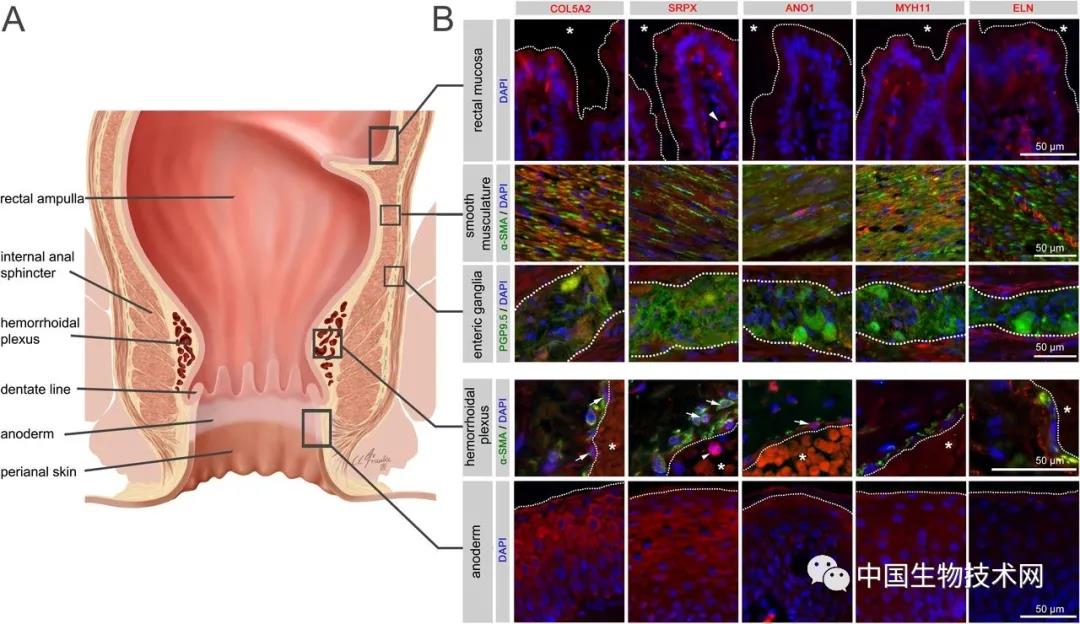

痔疮是临床上一种最常见的肛门疾病,根据发生部位的不同,可分为内痔、外痔和混合痔。无论是哪种,痔疮都在影响全球很大一部分人群。因此,也就有了“十男九痔,十女十痔”的...